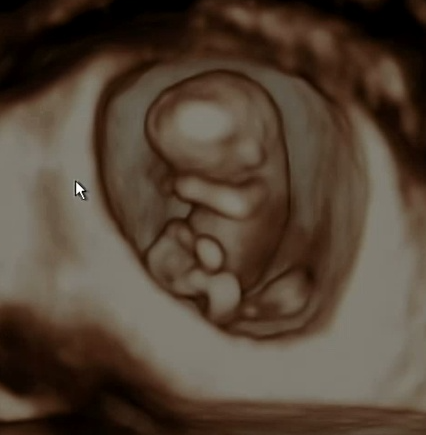

처음 임신을 알게된건 임신 극초기때였습니다. 계속 기다리던 아기라 계속 테스트기를 하기도 했고 느낌이 이상해 산부인과를 방문했지만 초음파로는 보이지 않았고 피검사로 임신을 했다는 사실을 알게됐습니다. 5주가 됐을무렵 아기집이 생기고 난황이 보였습니다.

점점 커갈때마다 임산부는 힘들어하고 아기도 걱정되고 심하게 배가 땡기고 아플때마다 병원을 방문했습니다. 조금씩 출혈이 초음파에서 잡히기도 했고 의사선생님께서는 계속 눕거나 안정을 취해야 한다고만 하셨습니다. 토를 안하려고 신맛이 나는 사탕,젤리를 자주 먹었지만 갑자기 나오는 토는 참을수가 없습니다. 밖에 나갈때는 비닐이 필수였습니다.